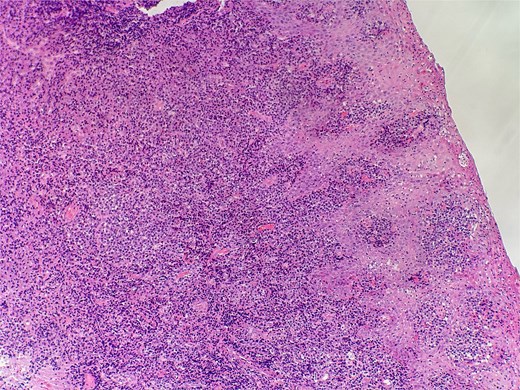

On clinical examination, harsh stridor with increased work of breathing was noted. Flexible nasoendoscopy demonstrated generalized supraglottic oedema with impending upper airway obstruction. Intravenous dexamethasone was commenced. A surgical tracheostomy with laryngeal biopsies under general anaesthetic was carried out. Histological examination (Figs 1 and 2) demonstrated hyperplastic, hyperkeratotic squamous mucosa with reactive atypia and an underlying dense polyclonal plasmocytic inflammatory infiltrate. No granulomata, prominent eosinophils, or stigmata of vasculitis were seen. Connective tissue disease screening demonstrated normal antinuclear antibody levels with positive perinuclear anti-neutrophil cytoplasmic antibodies. Anti-proteinase 3 levels returned as 3.7 IU/ml (range 0–1.9), while antimyeloperoxidase levels were normal. Rheumatology was consulted, and a provisional diagnosis of PCM was made. Serial laryngoscopy demonstrated resolution of the oedema, with the supraglottis regaining a normal appearance despite gradual tapering of the intravenous dexamethasone. A tracheostomy capping trial was successful. The patient was decannulated uneventfully and discharged on oral prednisolone. Three months later, he was maintained on 5 mg prednisolone—attempts to taper any further caused symptoms recurrence. Outpatient referral was made to Rheumatology for medical management with steroid-sparing therapy. Unfortunately, the patient was lost to follow-up due to failure to attend for outpatient review.

Slide from index presentation under higher magnification again demonstrating plasmocytic infiltration.